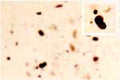

Our Anti-Alpha-synuclein rabbit polyclonal primary antibody detects human, mouse, and rat Alpha-synuclein, and is whole serum. It is validated for use in IHC-Frozen.

Immunohistochemical analysis of human brain indicates a high level of specificity for this antiserum. This antibody is known to react with human, mouse and rat alpha synuclein. Other species have not yet been tested.